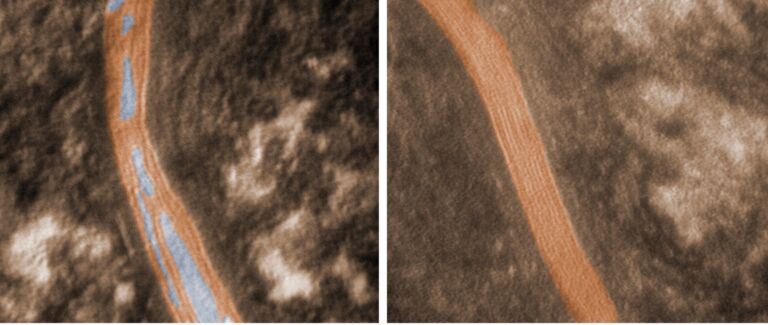

Microscopy Services setzt das patentierte Analyseverfahren Lipbarvis® (Lipid Barrier Visualisation, LBV) ein, um die epidermale Hautbarriere direkt ohne invasive Probenahmen untersuchen zu können.